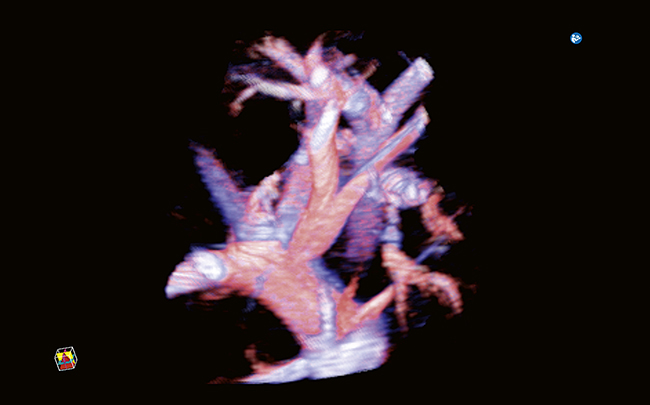

Imaging 2D, 3D e 4D

Architettura Radiance ottimizzata per imaging volumetrico

Rendering 3D/4D ad alta fedeltà

Imaging volumetrico per follow-up e consulenze multidisciplinari